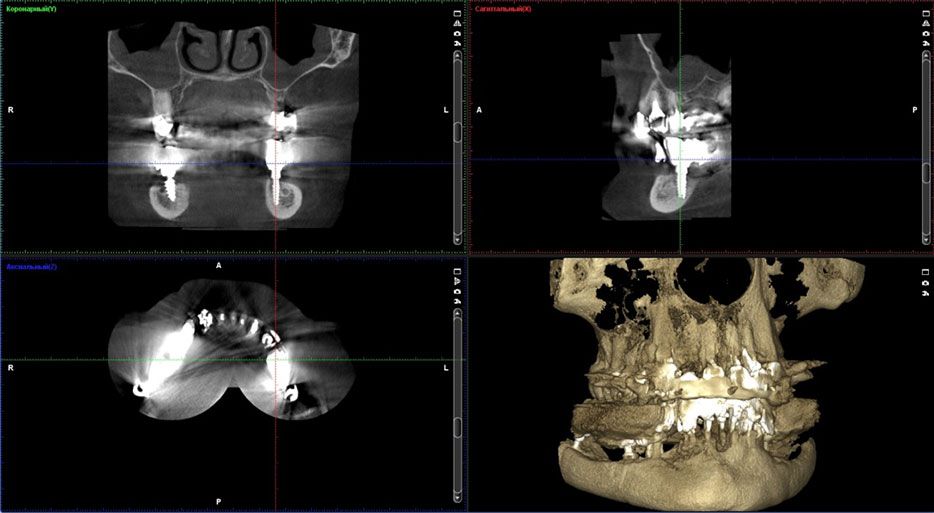

Fig. 7. The computer tomography 6 months after the implant insertion

Fig. 8. The computer tomography 6 months after the implant insertion in the posterior region of the mandible.

Fig. 9. The computer tomography 6 months after the implant insertionin the posterior region of the mandible: implants inserted detouring the inferior alveolar nerve and mandibular canal.

The CT examination proved the bone tissue of type I according to the Lekholm and Zarb classification in this case.The posterior regions where the implants are planned to be inserted the alveolar crest was 10,57 mm in width and 11,90 mm in height. The distance between the cortical plate and the mandibular canal was only 4,91 mm.Such minimal extent of the bone on the side area in the posterior mandibular region allows to place narrow implant with 3,0 mm in width to avoid the contact with the inferior alveolar nerve. Otherwise dental implantation in this conditions is not available without bone augmentation or/and the inferior alveolar nerve transposition.

In this case placement of the implants in the posterior area detouring the mandibular canal was only possible after providing of the computer tomography in order to pinpoint the placement of the canal and consequent surgical navigation template preparation.The dental implantation surgery was planned virtually in the DDS-Pro programme using the computer tomography results, model scans and wax-up. It has been decided to manufacture the permanent orthopaedic construction supported by 6 implants.

It was clinically checked for implant stability, absence of unfavorable effects during percussion test, the absence of pain syndrome around the implants and absence of neurosensory deficiency. After inserting the implants a computer tomography was done to ensure the correct placement of the implants in the mandible.

By means of CT it was determined that the bone loss around inserted implants is absent around the implant and that the loss of bone tissue during the period of the implant loading does not exceed allowable limits.